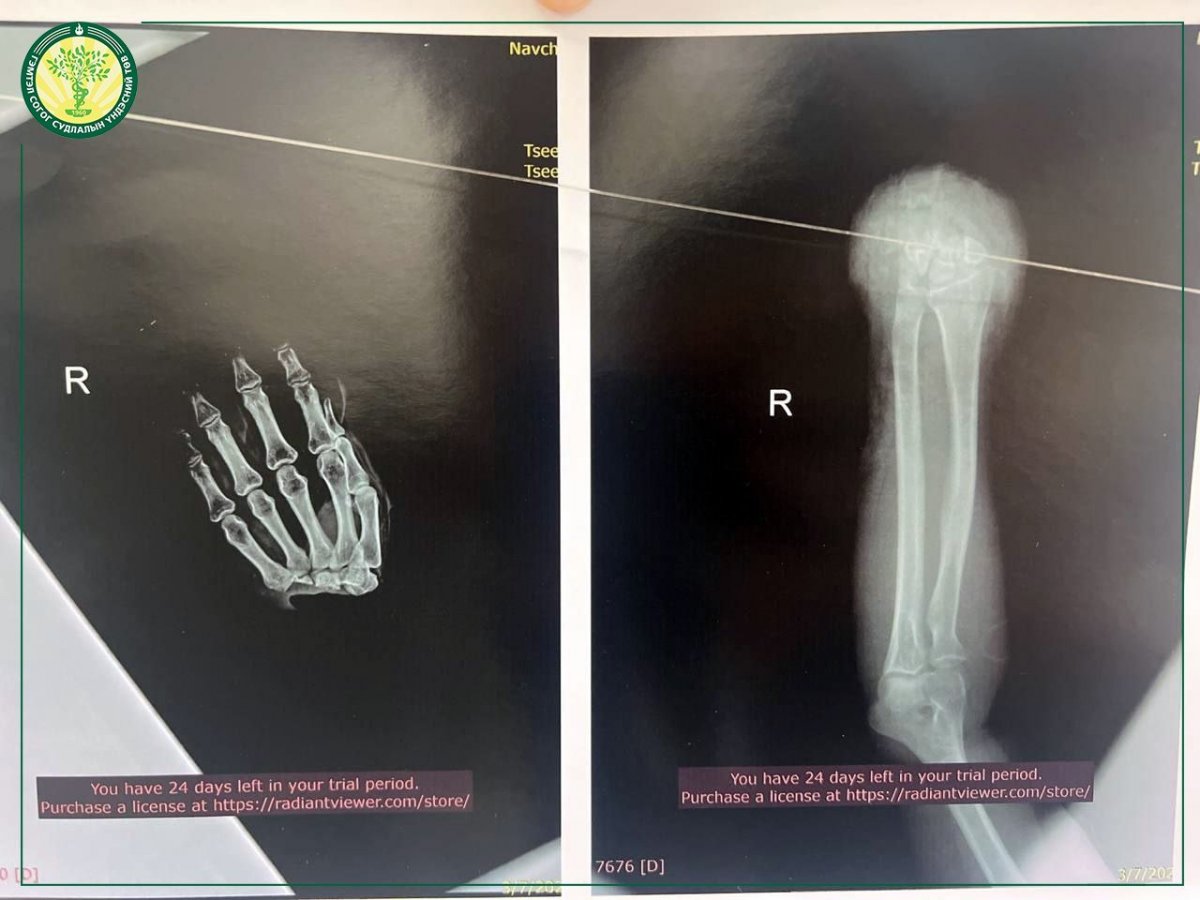

Эмч нар мах зорогч машинд хэрчигдэж, бугуйн хэсгээр бүрэн тасарсан гарыг эргүүлэн залгаж, одоо өвчтний шарх бүрэн эдгэрч, үйл ажиллагаа нь сэргэж эхэлсэн байна.